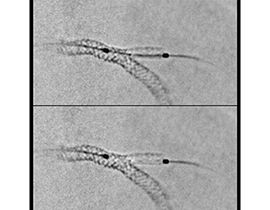

Die automatische Segmentierung von Knochen und Gefäßen und die Mittellinienverfolgung durch den Gefäßverschluss ermöglichen eine schnelle Planung anhand von präoperativen CT- oder MR-Bildern. Durch diese Kombination präoperativer CT- oder MR-Bilder mit Mittellinienverfolgung und Durchleuchtung in Echtzeit können Spezialisten außerordentlich gut sehen, wo die Rekanalisation vorgenommen werden muss und wo sich die Einstichstelle befindet, ohne die Kontrastmittelmenge erhöhen zu müssen.

Vessel ASSIST bietet eine präzise und einfache anatomische Segmentierung und genaue Gefäßquantifizierung anhand von 3D-Volumen. Zudem ermöglichen die erweiterte 3D-Roadmap und erweiterte Bildführungsfunktionen für die frontale und laterale Ebene das sichere Führen von Kathetern.